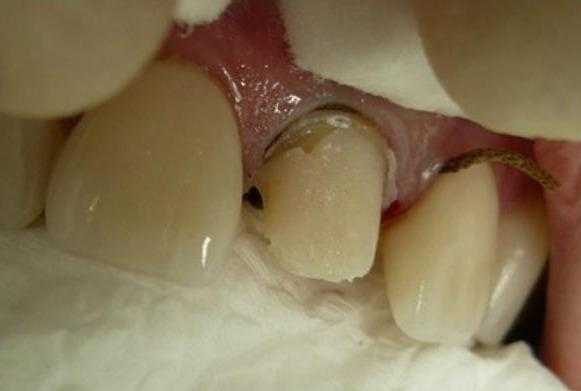

Пациентка М., 35 лет, обратилась в клинику с жалобами на расцементировку коронки из оксида алюминия на 2.1. Объективно: коронка имела подвижное положение на культе зуба 2.1 и без усилий извлеклась. Отмечался откол 1/3 культи зуба (внутренняя часть коронки была заполнена отделившимся фрагментом).

Дефект культи 2.1 зуба

Зуб в прошлом подвергался эндо лечению с последующим восстановлением с использование полимерного штифта. Отмечалось полное сохранение полимерного штифта на всем протяжении. Откололась только внутренняя поверхность коронки с фрагментом культевого материала.

Поверхность культи зуба была слегка препарирована с целью удаления малонадежных фрагментов композитного культевого материала. После этого по адгезивному протоколу нанесли кислоту на 15 секунд, обильно смылы, оставили поверхность слегка увлажненной и нанесли адгезивную систему. Я воспользовался адгезивом All Bond 3 (Bisco IL, USA). Это универсальный адгезив двойного отверждения, у него изменена структура полимерной матрицы и он максимально стабилен на дентинной субстанции после полимеризации за счет своей гидрофобности. После подготовки и полимеризации поверхность дентина имеет блестящий вид. Это хорошо.

Подготовленная культя зуба к восстановлению

Культя, восстановленная по коронке